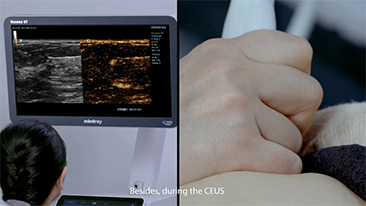

Mindray Resona Genel G?rĂŒntĂŒleme ??zĂŒmleri, kapsaml? alt b?lĂŒm uygulama problar? ve verimli klinik uygulama ara?lar? arac?l???yla, klinisyenlerin daha do?ru ve verimli tan? ve tedavi sonu?lar? elde etmesine yard?mc? olur.